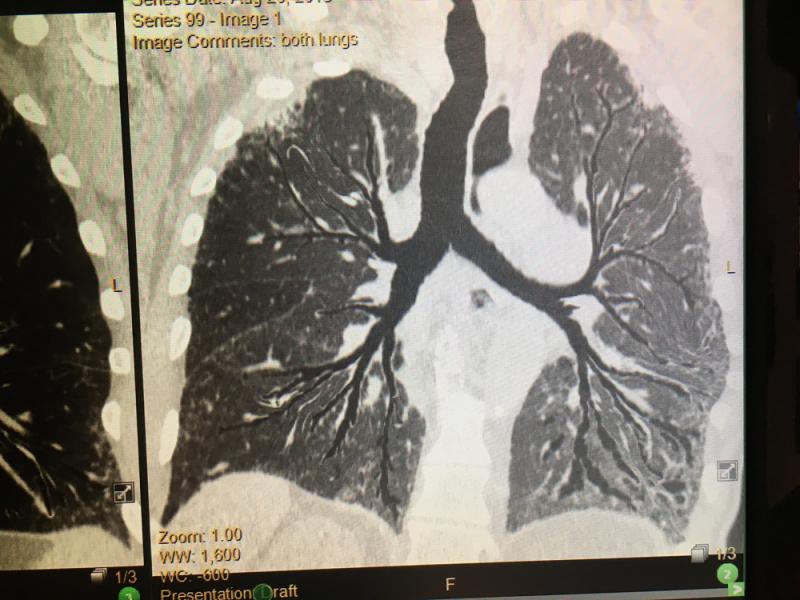

This is a lung X-ray reviewed automatically by artificial intelligence (AI) to identify a collapsed lung (pneumothorax) in the color coded area. This AI app from Lunit is awaiting final FDA review and in planned to be integrated into several vendors' mobile digital radiography (DR) systems. Fujifilm showed this software integrated as a work-in-progress into its mobile X-ray system at RSNA 2019. GE Healthcare has its own version of this software for its mobile r=ray systems that gained FDA in 2019.

Here are images of some of the newest new medical imaging technologies displayed on the expo floor at the Radiological Society of North America (RSNA) 2019 meeting. Use the slider images below to see the photos.